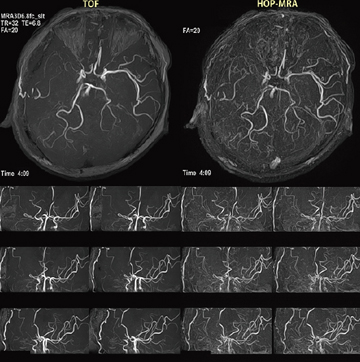

HOP-MRAの概念を図4に示す。TOF法は,収集断面に対し直交方向に流入する血流の描出に優れる。その反面,面内に回り込む血管や平行に流れる血流の描出が困難な場合がある。FSBBは,TOF法の弱点を補い,方向依存性の少ない血流描出を可能にした。3D-FE法をベースにして,繰り返し時間(TR)内でTOF法の信号とFSBBの信号をダブルエコーで収集する。こうして得られたデータを画像演算することで,微細な血流信号を高信号に描出するのである(図5,6)。

図5 HOP-MRAとTOFのシグナル・プロファイリングカーブの比較

PCA末梢血管CNRは,TOF法に比べHOP法で増大している。

縦軸は背景に対するCNR=(S-Sback)/noiseSDを表す。

図6 1.5TのHOP-MRAの臨床例:右中大脳動脈閉塞,右STA-MCA吻合術の術後評価

(画像ご提供:杏林大学医学部放射線医学教室・土屋一洋先生)